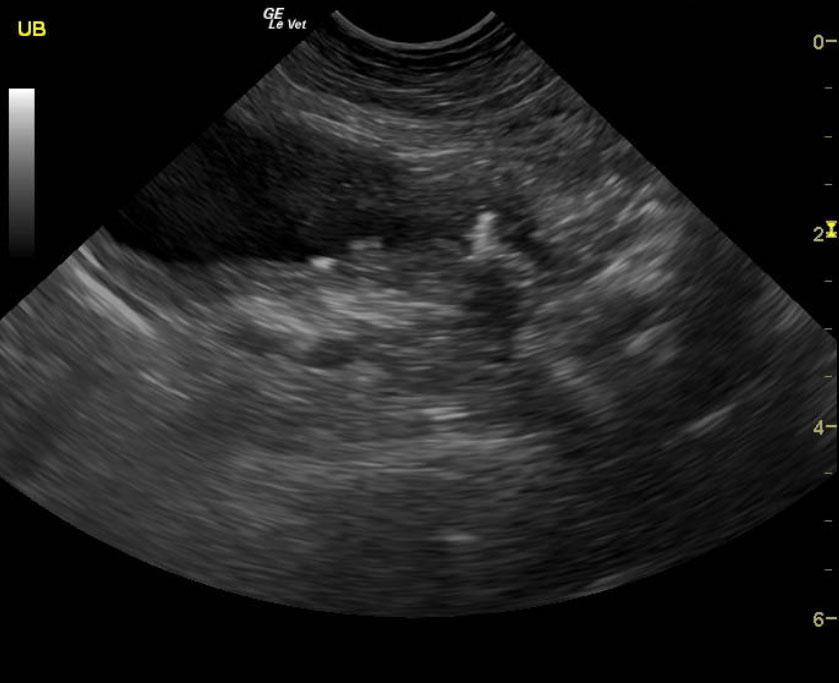

Mineralizing prostatic mass extending into the preprostatic urethra and trigone with local iliac lymphadenopathy. These images are strongly suggestive for metastatic prostatic carcinoma.

The prostate presented multi focal mineralization with swollen contour with minor polypoid changes and hyperechoic surrounding fat. This projected into the trigone. The mineralizing, prostatic mass measured 2.9 cm and infiltrated into the preprostatic urethra and likely post prostatic urethra. Iliac lymphadenopathy was noted.

Comet-tail pattern was noted in the transdiaphragmatic view of the thoracic cavity. Chest radiographs would be warranted to assess for pulmonary disease or potential metastatic disease.